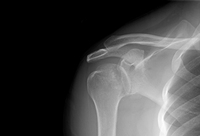

Radiografia com incidência anteroposterior de ombro mostrando luxação anteroinferior

Acervo pessoal do Dr. Paul Novakovich